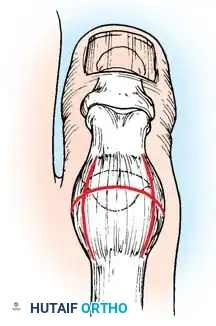

2. Jones Procedure (EHL to First Metatarsal Neck)

* Rationale: Corrects flexible clawing of the hallux and elevates the first ray.

* Technique: Transect the EHL at the IP joint. Reroute it through a drill hole in the neck of the first metatarsal and suture it back onto itself. The IP joint of the hallux must be arthrodesed to prevent a secondary drop-toe deformity.